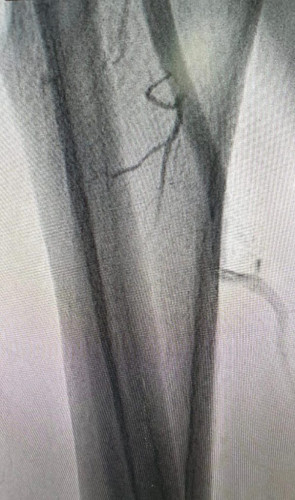

نجح بفضل الله فريق طبي في مركز القلب بمستشفى القريات العام في علاج مريض كان يعاني من تضيق شديد في الشريان الأبهر وشرايين الحوض حيث أجريت له عملية قسطرة ناجحة لشرايين الأطراف السفلية و تكللت -بحمد الله وتوفيقه- بالنجاح. والمريض بحالة صحية جيدة ومستقرة ولله الحمد .

حيث تعتبر حالة من نوعها تجرى في قسم القلب وتأتي ضمن مراحل التشغيل التدريجي لهذا الصرح الطبي النوعي في صحة القريات ، والذي سيقدم خدمات طبية تخصصية لأهالي المنطقة عبر فريق عمل متخصص ومتكامل.